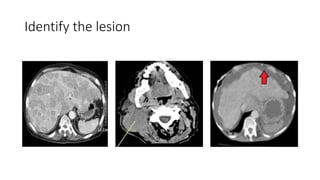

Identify the lesion